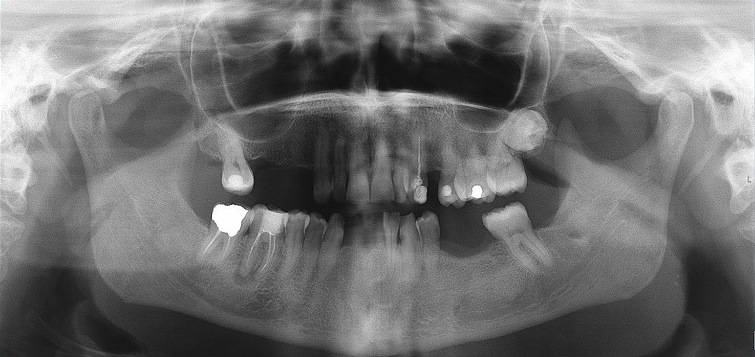

A ortopantomografia não revelou qualquer envolvimento dos tecidos ósseos (Figura 3).

Figura 3 Ortopantomografia no momento da avaliação demonstrando ausência de envolvimento ósseo da lesão